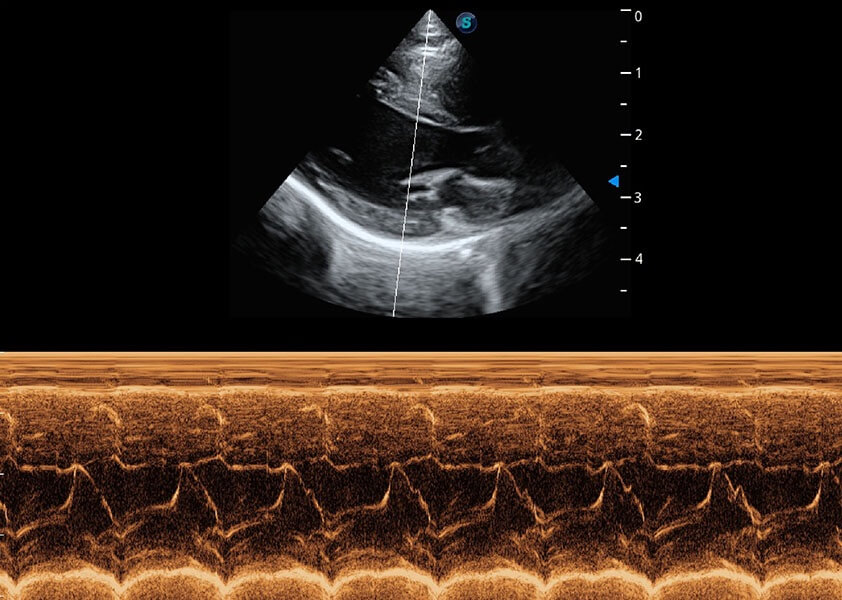

ProPet 60 作为一款高端台式动物超声设备,为动物医生的日常诊断提供了一系列贴合动物临床需求、解决临床实际问题的高级成像功能。凭借全系列高清探头,满足医生对腹部、心脏、生殖、浅表、肌骨等成像的所有需求,切实帮助您提升检查效率,提高诊断信心。

动物是人类最亲密的朋友和最值得信赖的伙伴。db真人体育官网也一直致力于探索动物专用的超声影像解决方案。 全新推出的ProPet系列,是db真人体育官网在动物超声影像智能化、专业化、精准化的一次跨越式革新。动物不能用言语来表述自己的不适,通过超声影像,ProPet系列搭建了动物医生与不同物种沟通的“桥梁”,为动物医生注入了“治愈之力”。